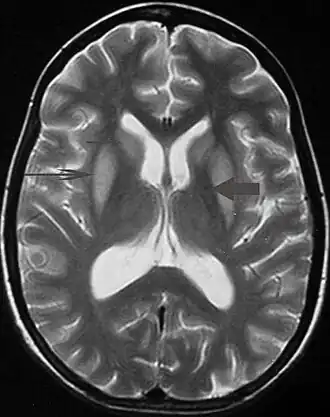

| Ressonância de um paciente com parkinsonismo severo. | |

Tremor pode ser um sintoma associado a distúrbios nas partes do cérebro que controlam os músculos de todo o corpo ou em áreas específicas, tais como as mãos. Dentre os problemas neurológicos que podem produzir tremor incluem-se: hipertireoidismo, esclerose múltipla, acidente vascular cerebral, traumatismo craniano, doença renal crônica, doenças neurodegenerativas que danificam ou destroem partes do tronco cerebral ou o do cerebelo, sendo a doença de Parkinson o mais frequentemente associados com tremor. Transtornos neurológicos que causem tremor são chamados de parkinsonismo.